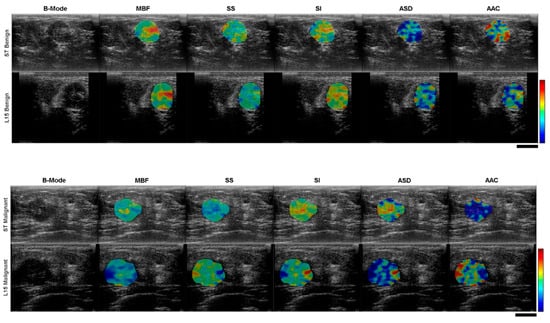

2.2. Ultrasound Data Analysis